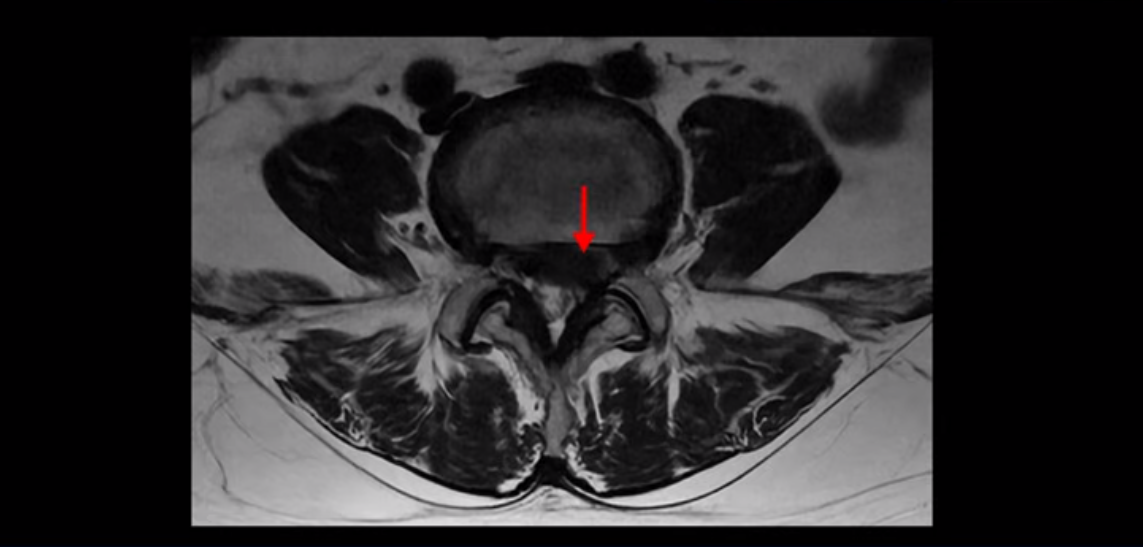

단면을 보면 디스크 수핵은 왼쪽으로 심하게 밀려 나와 있고

좌우 뒤쪽에는 황색 인대가 두꺼워져 있습니다.

앞에서는 디스크 수핵이 신경 공간으로 침범하고 뒤에서는 두꺼워진 인대가 신경 공간을 좁히고 있습니다.

이렇게 신경 공간이 좁아진 것을 협착이라고 합니다. 왼쪽으로 신경 구멍이 더 좁아져 있으니까 처음에는 왼쪽 엉덩이와 다리가 아팠는데 몇 년 동안 주사 맞으면서 버티다 보니까 오른쪽 다리까지 아프게 됩니다. 결국 양쪽 다리가 너무 아파서 5분 걷기도 힘들어지게 됩니다.